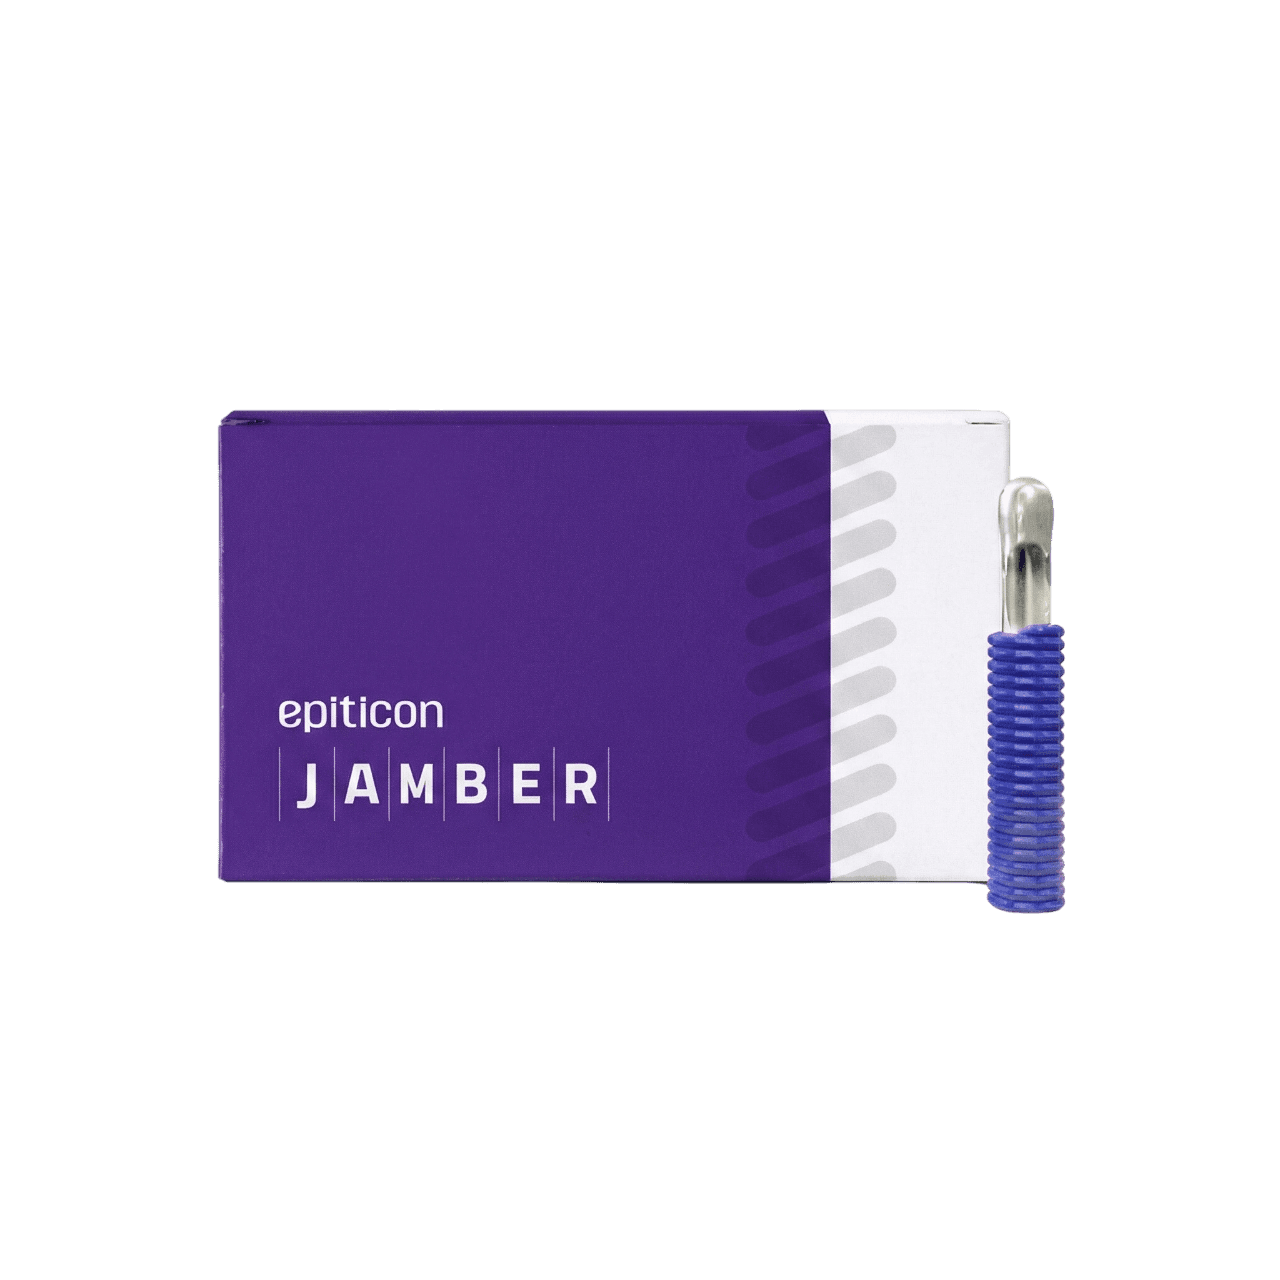

Product

Thread Lifting

360° Clean Line